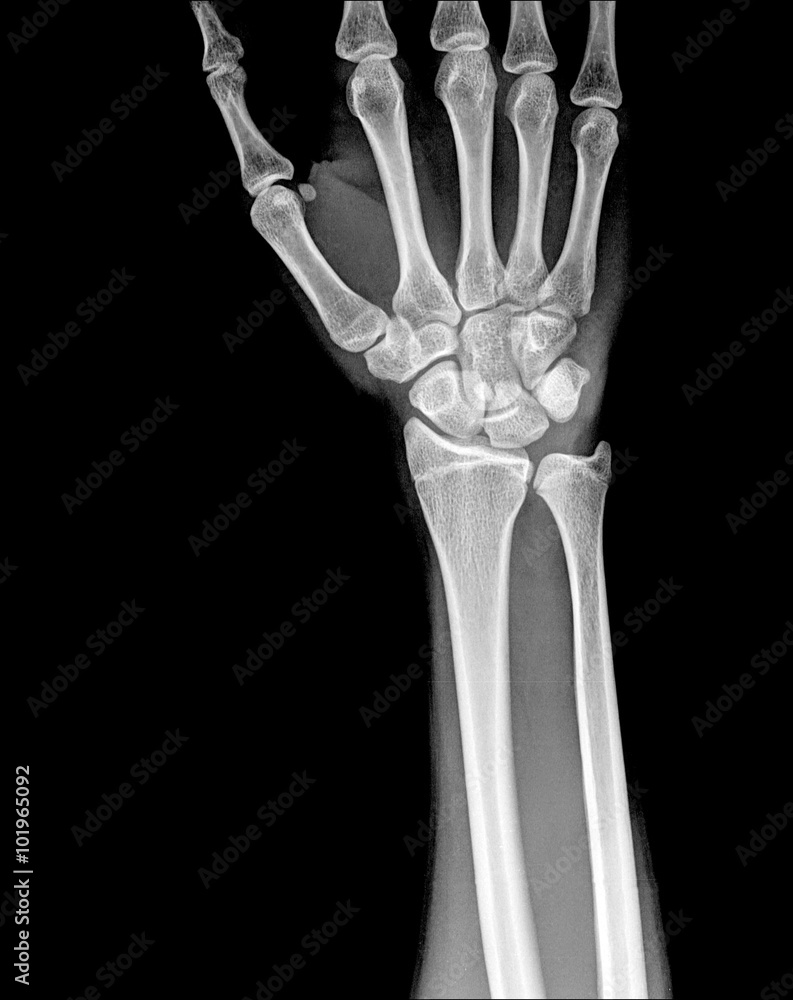

From stock.adobe.com

Fracture distal radius (wrist bone) Stock Photo Adobe Stock Radius Wrist Bone Sticking Out This is called an open fracture and needs urgent surgery. What is a fracture of the distal radius? Colles' fractures, the most common type of distal radius fractures, which occur when falling on an outstretched hand, where the hand is extended backward on the wrist, and. Diagnosis is made clinically and radiographically. It can also happen in a car accident,. Radius Wrist Bone Sticking Out.